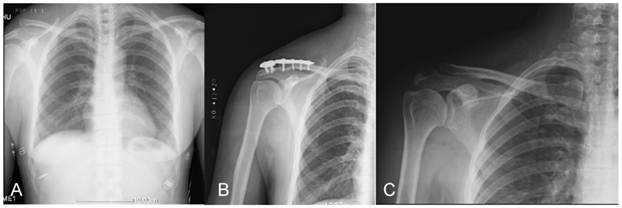

Figure 2

A 43-year-old man fell from motorcycle. (A) A preoperative radiograph of his chest showed acute complete acromioclavicular joint dislocation. (B) A postoperative radiograph of the same patient showed the ideal reduction of acromioclavicular joint and correct position of the MAAP. (C) Three months after open reduction and internal fixation. The MAAP was removed without any complication.

Postoperative radiograph follow-ups showed two older patients had screw loosening with degenerative changes and slight loss of reduction of the acromioclavicular joint (cases 7 and 10). No patient had a MAAP broken and complete dislocation of the acromioclavicular joint during follow-up (Fig. 2). There were no signs of redislocation of joint. Apart from a few patients ' pain symptoms, no other complications were observed. In addition to a patient because of frequent shoulder pain and limited range of motion of shoulder joint, all patients have returned to their preoperative work without any limitations.